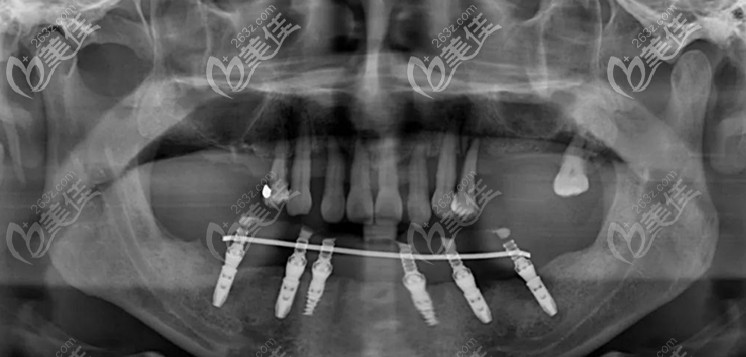

考慮到顧客的身體耐受力,此次的手術(shù)分兩次進(jìn)行,先進(jìn)行下頜即刻種植手術(shù),即拔即種、當(dāng)天就能戴牙使用。

▲下頜的6顆即刻種植牙

第二次在進(jìn)行上半口的上頜穿翼板VIIV即刻種植技術(shù),整個手術(shù)進(jìn)行了2個多小時,在周院長和蔣院長的配合下,6顆植體都按照既定設(shè)計方案植入骨內(nèi)。

▲上半口兩顆傾斜的植體就是穿翼板種植技術(shù)

其中有2顆是高難度的穿翼板植體,避開了錯綜復(fù)雜的神經(jīng)血管,此技術(shù)不植骨、不等待、出血量少,突破了傳統(tǒng)種植牙對牙槽骨條件的限制。